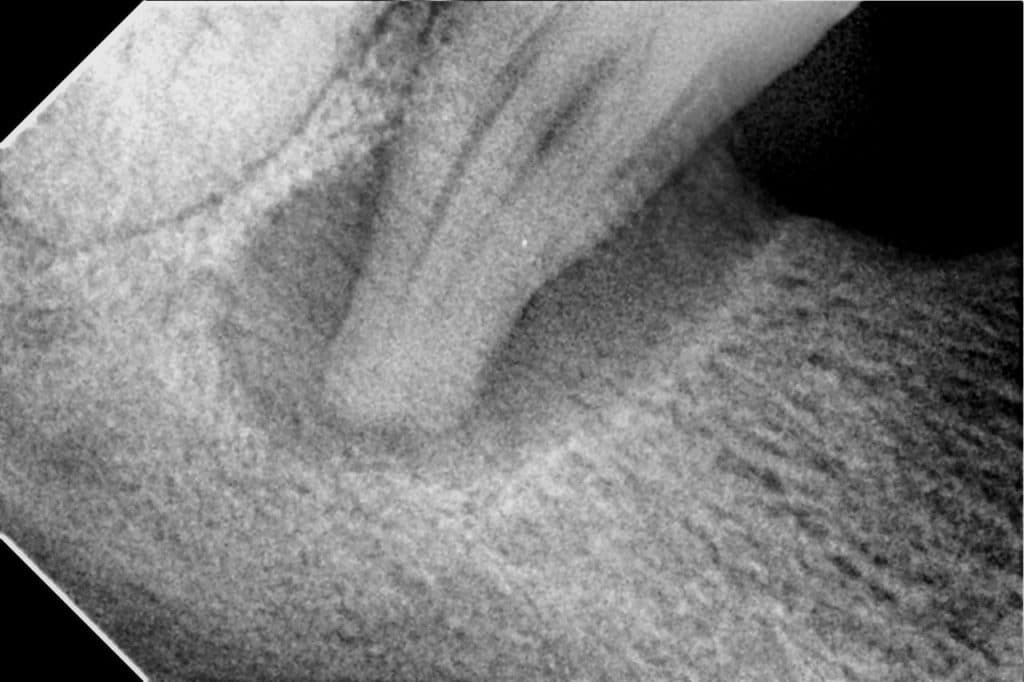

Follow up after 7 months

Follow up after 12 months